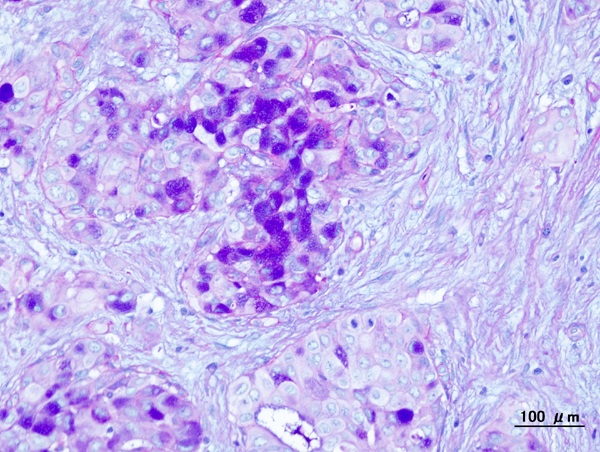

Pleomorphic Adenoma

Pleomorphic adenoma is a benign tumor made up of both epithelial and stromal tissue.

Pleomorphic adenoma is the most common salivary gland tumor.

Pleomorphic adenoma appears as a moving, painless mass that is constrained to the angle of the jaw.

Histologically pleomorphic adenomas have a myxoid component and a stromal component.

Pleomorphic adenoma is associated with the PLAG1 gene mutation.

Treatment of pleomorphic adenoma is surgical resection.

Small islands of tumor that extend through the tumor capsule frequently result in an incomplete resection.

There is a high recurrence rate for excised pleomorphic adenomas.

Rarely the benign pleomorphic adenomas may develop into their malignant counterparts carcinoma-ex pleomorphic.